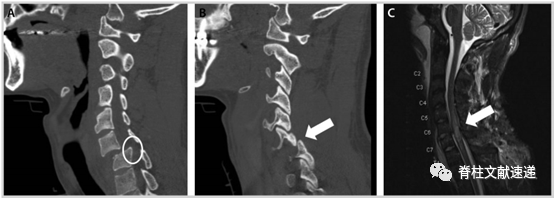

X线检查是最基本的影像学检查,可以帮助我们识别患者是否存在脊柱骨折、脱位、脊柱的稳定性等情况,CT检查可比X线能更加全面的显示脊柱骨性结构的损伤,并能够观察到是否有骨块突入椎管内,许多研究表明,在筛查疑似或有脊柱损伤风险的急性损伤患者时,CT比X线更具优越性,其阴性预测值接近100%,特别是涉及到临床不稳定损伤或需要干预的损伤。

MRI能够准确的判断脊柱、脊髓损伤程度,特别是当CT提示脊髓、椎间盘等可能存在损伤或无法解释的神经系统检查时,MRI可以帮助我们早期诊断、估计预后(椎管内出血(> 1cm长)以及T2信号纵向改变> 3cm与预后不良有关,正常的MRI结果通常预示患者能够恢复正常)及制定治疗决策。

图注:图A、B为C6-7脱位的CT结果,图C为MRI的T2加权像结果显示以C6-C7为中心的外伤性脊髓损伤, C5至T1均存在不同程度的脊髓信号异常。